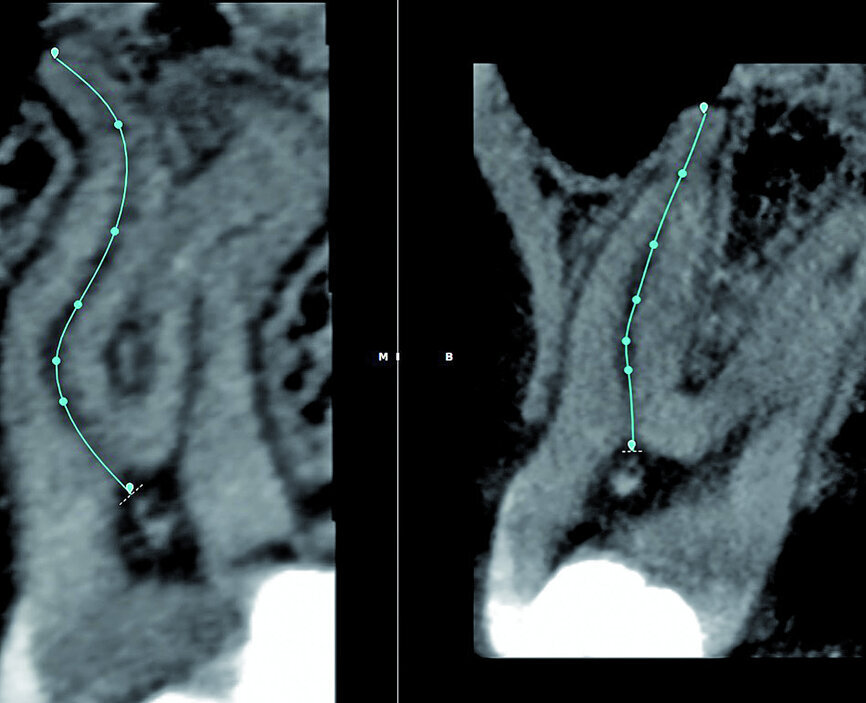

With the fourth step, ‘3D Canal Anatomy’, the software made a proposal of the canal anatomy (Fig. 7), but the operator can make corrections according to the canal configuration that can be viewed in different planes in the software. Figures 8 to 10 show the mapping of the palatal, mesiobuccal, and distobuccal root canal systems.

During the fifth step, ‘Treatment Plan’, the software projected ISO size 06 instruments into the canals (Fig. 11), which allowed the operator to visualise the internal anatomy of the canals, check straight line access, and modify the proposed access if necessary. A rubber stop on the files can then be digitally adjusted to a coronal reference point of choice that will then indicate the proposed working length for each root canal system. This view can also be rotated in 3-D to alert the operator of the angle and direction of curvatures in the root canal systems (Fig. 12). The step after ‘treatment plan’ is to select a master file from a preloaded database of endodontic file systems that will most likely result in optimal canal preparation for that specific shape or diameter of a canal. Considering the s-shaped curvatures in all three root canal systems as well as the sharp curvatures in different planes, it was decided to use the Primary WaveOne Gold file (25/07) in the palatal canal and the Small WaveOne Gold file (20/07) for root canal preparation in the two-challenging buccal root canal systems (Fig. 13). The selected instruments were then displayed in the root canal systems and the operator again digitally rotated and visualised the root canal anatomy in 3-D (Fig. 14).

Fig. 7: The 3D Endo Software proposal of the canal anatomy that can be corrected by the operator, according to the canal configuration viewed in different planes in the software. In most cases, the proposal is very good but in this case it was not accurate because of the multi-planar canal anatomy.

Fig. 8: Corrections made for the palatal root canal according to the canal configuration that can be viewed in different planes in the software.

Fig. 9: Corrections made for the mesiobuccal root canal according to the canal configuration that can be viewed in different planes in the software.

Fig. 10: Corrections made for the distobuccal root canal according to the canal configuration that can be viewed in different planes in the software.